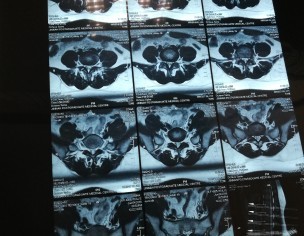

Attaching my MRI reports (MRI was in July). Everyone told me there is nothing serious just go for painkillers and physiotherapy. I was taking naproxen and was on physiotherapy from last 2 months. But still, there is no improvement. Sometimes I face severe back pain. So can someone please guide me what to do now? Please don't suggest me any treatment which is expensive as already invested a lot but all in vain. Is this disc herniation? Is it curable? I am seriously worried about it.